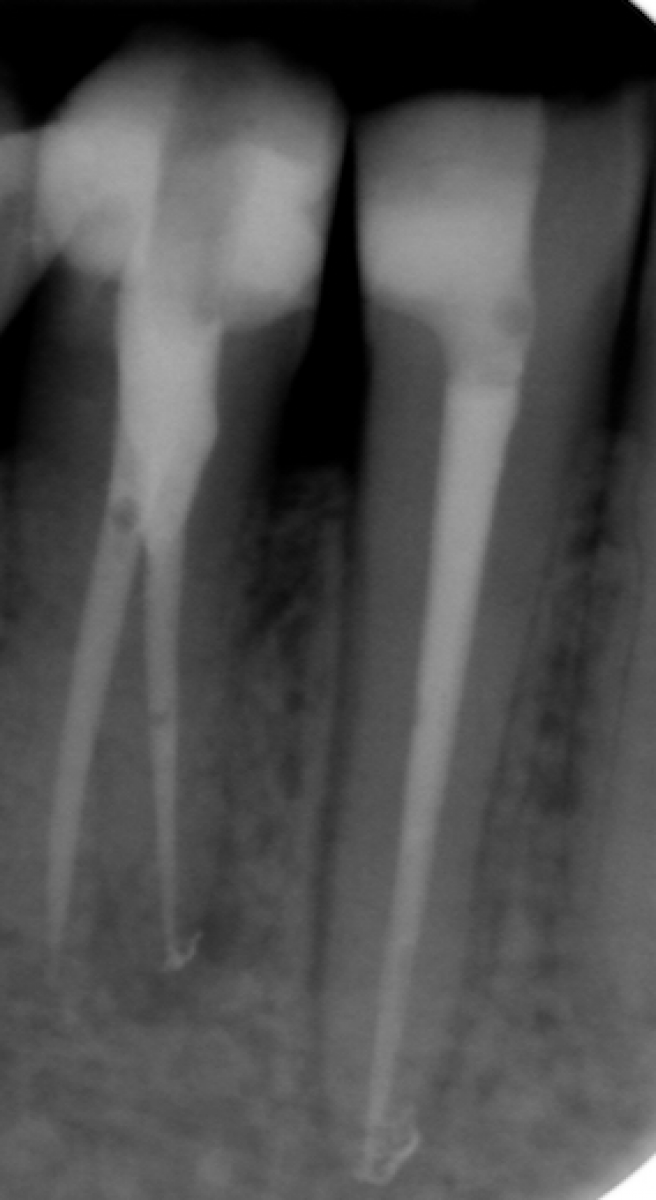

The gutta-percha point inserted into the root canal properly, adapting it to a size almost equal to the one employed to shape the apical terminus. Not wider, not smaller. Here are exposed a couple of cases made by shaping the root canal with a NiTi instrumentation technique and followed up for 9 to 12 months (Fig. 1-6).

It’s encouraging its easy handling and quite precise adaptation to the apical part of the root canal. The periapical healing, assessed by 2D-Rx, is considered satisfactory but further analysis and clinical studies related to these particular cements should be performed to confirm the first encouraging results.